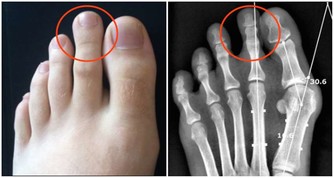

3、指甲修剪過短

手指甲或者是腳趾甲並不是剪得越短越好,如果露出嫩肉,

在洗衣做飯工作時會傷害到軟組織,

細菌也會通過破損處進入皮下進行生長繁殖,時間久了容易造成甲溝炎。

正確方法:修剪指甲時,最好留出一毫米左右,腳趾甲最好剪成方頭。